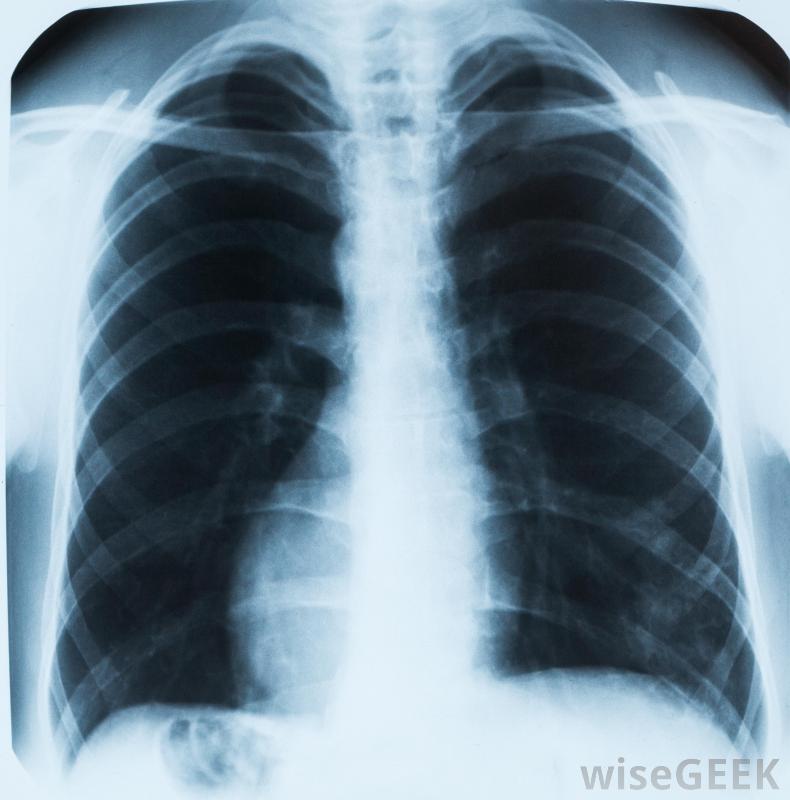

肺部的X光片可以帮助医生诊断肺结核几种不同的结核分枝杆菌菌株都能引起感染。当被感染者咳嗽或打喷嚏时,这种细菌就会通过空气传播,很容易被其他人吸入。在肺部,细菌附着在内层,可以长时间休眠。事实上,大多数人根本不会出现症状,因为他们的免疫系统很强,足以抵御病原体。很小的儿童,老年人,免疫系统减弱的人患活动性肺结核的风险最高。

肺结核的症状通常包括胸痛肺结核的第一个症状通常包括轻微的呼吸困难,偶尔咳嗽和喘息,以及胸痛。症状往往会在数周或数月内恶化,直到持续出现使人虚弱的问题。一个人可能开始咳血,发烧和发冷,而且一直感到疲劳。体重减轻,颈部淋巴结肿大,液体潴留也会发生。如果不治疗,细菌可以从肺部和淋巴结扩散到其他重要器官,引起非常严重的疾病。医生通常可以通过询问症状和对胸部进行诊断性成像扫描来诊断肺结核电脑断层扫描,肺部的斑块通常表现为发炎、疤痕和变色。也可以在实验室采集痰样并进行分析,以确认诊断。有时,可能需要收集肺组织样本以排除癌症大多数活动性肺结核可以通过一个疗程的抗生素治疗治愈。医生通常会开吡咯嗪酰胺,利福平,每天服用两到三种其他药物,至少持续六个月。患者在整个疗程中继续服用药物是很重要的,即使他们的症状很快好转,以确保细菌被完全根除。治疗期间和治疗后的频繁体检可以确认问题已得到解决